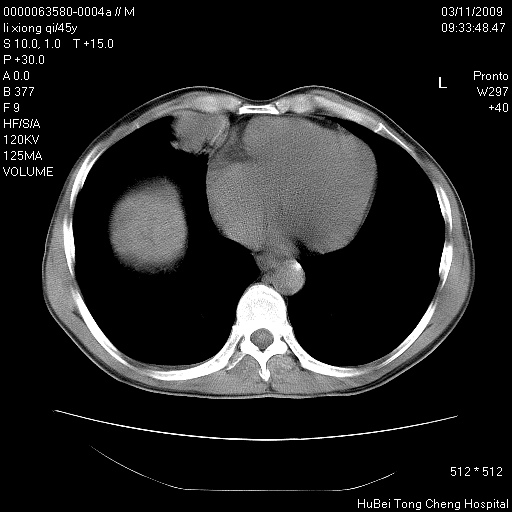

患者 男,45岁。胸痛,咳嗽伴痰中带血1月余。

临床诊断:肺结核?

胸部ct轴位平扫(层厚10mm,螺距1.5,重建间隔10mm),图像如下:

考虑肝癌肺转移